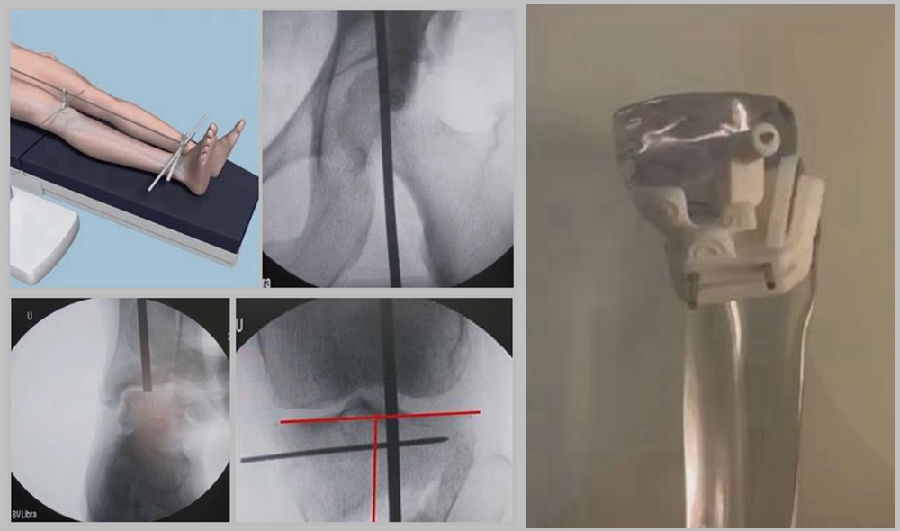

1、综合判断力线的方法

现在对于力线的判断大致通过以下几方面:①大体形态;②透视确定力线,连接股骨头中心、踝关节中心,看力线杆和膝关节中心的位置关系;③MPTA(胫骨平台关节线和胫骨侧机械轴夹角);④PSI。

(1)肢体外旋

一般来说在麻醉状态下肢体会处于外旋位,此时去测定力线的话往往需要将肢体放在旋转中立位,但是在内旋肢体的过程中会出现内翻应力,那么这种情况下判断力线会带来误差,所以通常建议大家要把手术床做一点旋转,让患肢处于自然的旋转中立位,这样再去判断力线就比较准确。

(3)力线验证未模仿负重应力

现在所谓的目标力线应该是模仿负重时的力线。做截骨时,通常会将力线轻度外移,如果没有考虑关节内畸形、韧带松弛或是软骨磨损,那么在负重时,在内侧副韧带撑开过程中,会出现力线偏移。所以要注意,手术中间在调整目标力线时,要以应力状态下为标准。